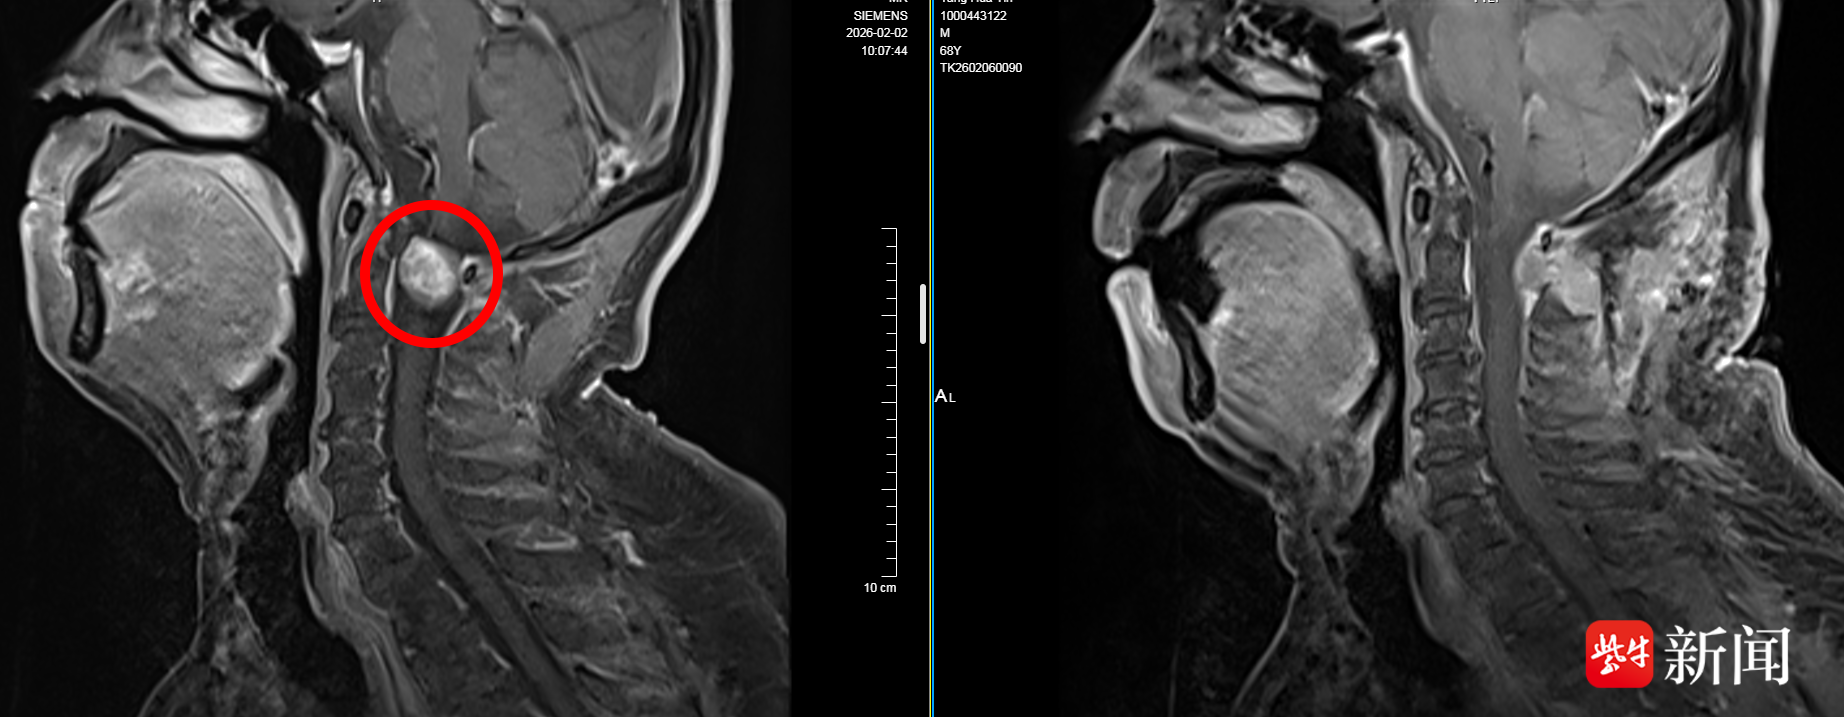

得知成惠林主任是区域脊柱脊髓疾病方面的诊疗专家,张先生随即前往泰康仙林鼓楼医院神经外科寻求治疗。神经外科团队联合放射科,通过头颅MRI增强扫描、CTA血管成像等检查,明确诊断张先生为“椎管内外占位性病变”,病变累及头颈交界区,紧邻颈髓及重要血管,手术风险很高。

左图红圈内是术前影像检查发现的肿瘤

复查MRI显示,张先生原先受压的脊髓已解除,肿瘤已被完整切除,无残留。经过一个星期的精心治疗和护理,张先生的头痛症状没有了,四肢活动自如。日前,他已顺利出院。

“他的肿瘤生长位置比较特殊,位于寰枢椎之间,解剖位置深、毗邻生命中枢,手术难度大、风险高,需在显微镜下精细操作,才能保护好神经血管结构。”成惠林主任表示,术后病理报告提示张先生所得肿瘤为神经鞘瘤。这是一种起源于神经鞘膜细胞的肿瘤,绝大多数是良性的,生长缓慢。但它如果长在颅颈交界区这样“寸土寸金”的地方,随着体积增大,轻则挤压脊髓和神经,引发疼痛、麻木,甚至瘫痪等严重后果。